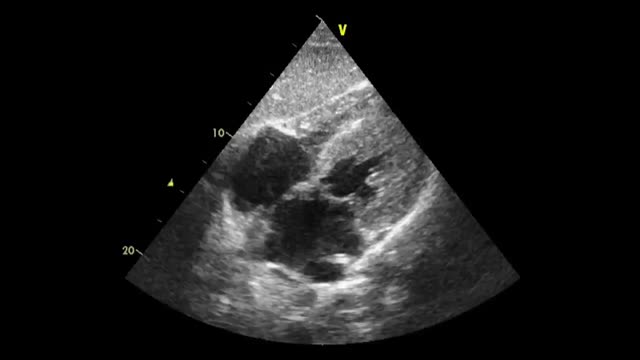

PreprocedureThe patient should lie supine in a slight semi-recumbent position. With a convex or phased-array probe, it is of paramount relevance to estimate the size of the pleural effusion to define whether thoracentesis is needed or safe, another procedure, or no procedure should be performed. While often eyeballed, a drainable pleural effusion may be defined when the distance between the visceral and parietal pleura is ≥10 mm.55 In addition, the ultrasonographic characteristics of the effusion should also be assessed based on the presence of septations, swirling debris (i.e., plankton sign) or pleural thickening. While anechoic effusions can be either transudative or exudative, those showing one or more of the aforementioned signs are often exudative and should prompt pleural fluid sampling (Fig. 3A and B).53 The distance from the skin to the parietal and visceral pleura should be measured using ultrasound to aid in the selection of an adequate needle length and estimate the depth of insertion (Fig. 3C). The diaphragm must also be delineated. Chest wall vessels should be excluded from the needle trajectory, which is assessed with a linear probe using color Doppler (Fig. 3D).56 Bilateral lung sliding should also be determined prior to the procedure.

Ultrasound-guided thoracentesis. A) A simple pleural effusion (asterisks), diaphragm (d) and lung (L) are delineated using ultrasound. B) A complex pleural effusion (asterisk) is observed; d, diaphragm. C) The best fluid pocket for thoracentesis is selected by measuring the distance from the skin to the pleural effusion (asterisk) and the effusion depth; L, lung; d, diaphragm. D) The intercostal vessels are delineated before cannulation using a linear transducer and color Doppler. E) The insertion site is marked on the skin. F) Dynamic ultrasound guidance for thoracentesis. Arrows, needle shaft; arrowhead, needle tip; asterisk, pleural effusion; L, lung. G) The guidewire (arrows) is observed within the pleural effusion (asterisks); d, diaphram. H). A central catheter (arrows) is observed within the pleural effusion (asterisks); L, lung.

The procedure can be performed under static or real-time ultrasound guidance. Although both techniques have proven to be useful, the static technique is preferable. The added effort and complexity of the real-time technique is rarely justified, as moderate or large effusions are easy to access, provided the pre-procedure scan is made correctly.56 Real-time guidance is best reserved for small or loculated effusions, where strict control of needle trajectory and depth is mandatory.56

With the static technique, and with the patient lying in the same position as the preprocedural scan, the best insertion site is selected with ultrasound and is marked with a pen on the skin (Fig. 3E). After disinfecting and infiltrating the target site with local anesthetics, the needle is advanced until pleural fluid is obtained. The needle should be inserted along the superior border of the rib to prevent inadvertent injury to the intercostal vessels that run along the inferior rib border.

In the dynamic technique, the needle is inserted in-plane and observed in real-time, entering the pleural space when pleural fluid is aspirated (Fig. 3F). A fully sterile technique is required to do so.

When evacuation of the effusion is needed, a pigtail catheter is typically inserted.57 In patients with non-complicated pleural effusions, pleural drainage using central venous catheters has proven useful and safe.58 Each time the Seldinger technique is used, the guidewire should be observed in the pleural space before passing the dilator (Fig. 3G). Then, the catheter is advanced and the guidewire is removed. Intrapleural placement of the catheter can also be confirmed by ultrasonography, following its course from the superficial soft tissues to the pleural cavity (Fig. 3H). Finally, the catheter is connected to a drainage system, which could be a water-seal chest drainage or a urinary bag collection system,58 interposing a Heimlich valve.

PosprocedureLung ultrasound is performed to rule out pneumothorax. A comparison with preprocedural scanning is helpful. Among the several well know ultrasonographic signs of pneumothorax, the hydro-point sign should also be actively investigated.59 The hydro-point defines the presence of hydropneumothorax and is best assessed with a convex or phased-array probe in basal lateral or posterolateral views of the thorax.60,61 This sign is depicted as contact between the pleural fluid and the artifacts of the intrapleural air, which does not show lung sliding61(Video 4). Chest radiography may be safely omitted in patients in whom a successful thoracentesis is performed and no ultrasonographic signs of pneumothorax are detected.